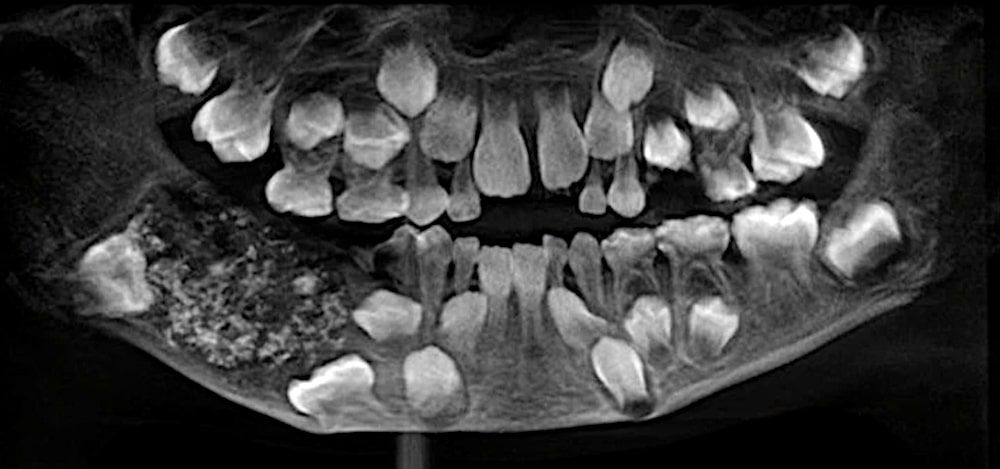

Les dentistes ont commandé une radiographie et un scanner, révélant une "structure semblable à une poche" dans la bouche du garçon, contenant 526 dents, a déclaré P. Senthilnathan, professeur de chirurgie buccale et maxillo-faciale au Saveetha Dental College and Hospitals. Les dentistes rapportent que la condition contractée par le pauvre garçon est connue sous le nom d'odontome composé, une forme de tumeur odontogène.

« Le tissu ressemblant à une tumeur a empêché la croissance des molaires permanentes chez le garçon, du côté affecté. Les rayons X et le scanner ont montré de multiples dents rudimentaires dans un tissu ressemblant à une poche », a déclaré Senthilnathan au New Indian Express.

« Les dents étaient de différentes tailles et variaient entre 0.1 mm et 15 mm », a-t-elle déclaré. « Certaines ressemblaient aux perles que l'on peut trouver dans les huîtres. Même la plus petite pièce avait une couronne, une racine et une couche d'émail, comme une dent ».